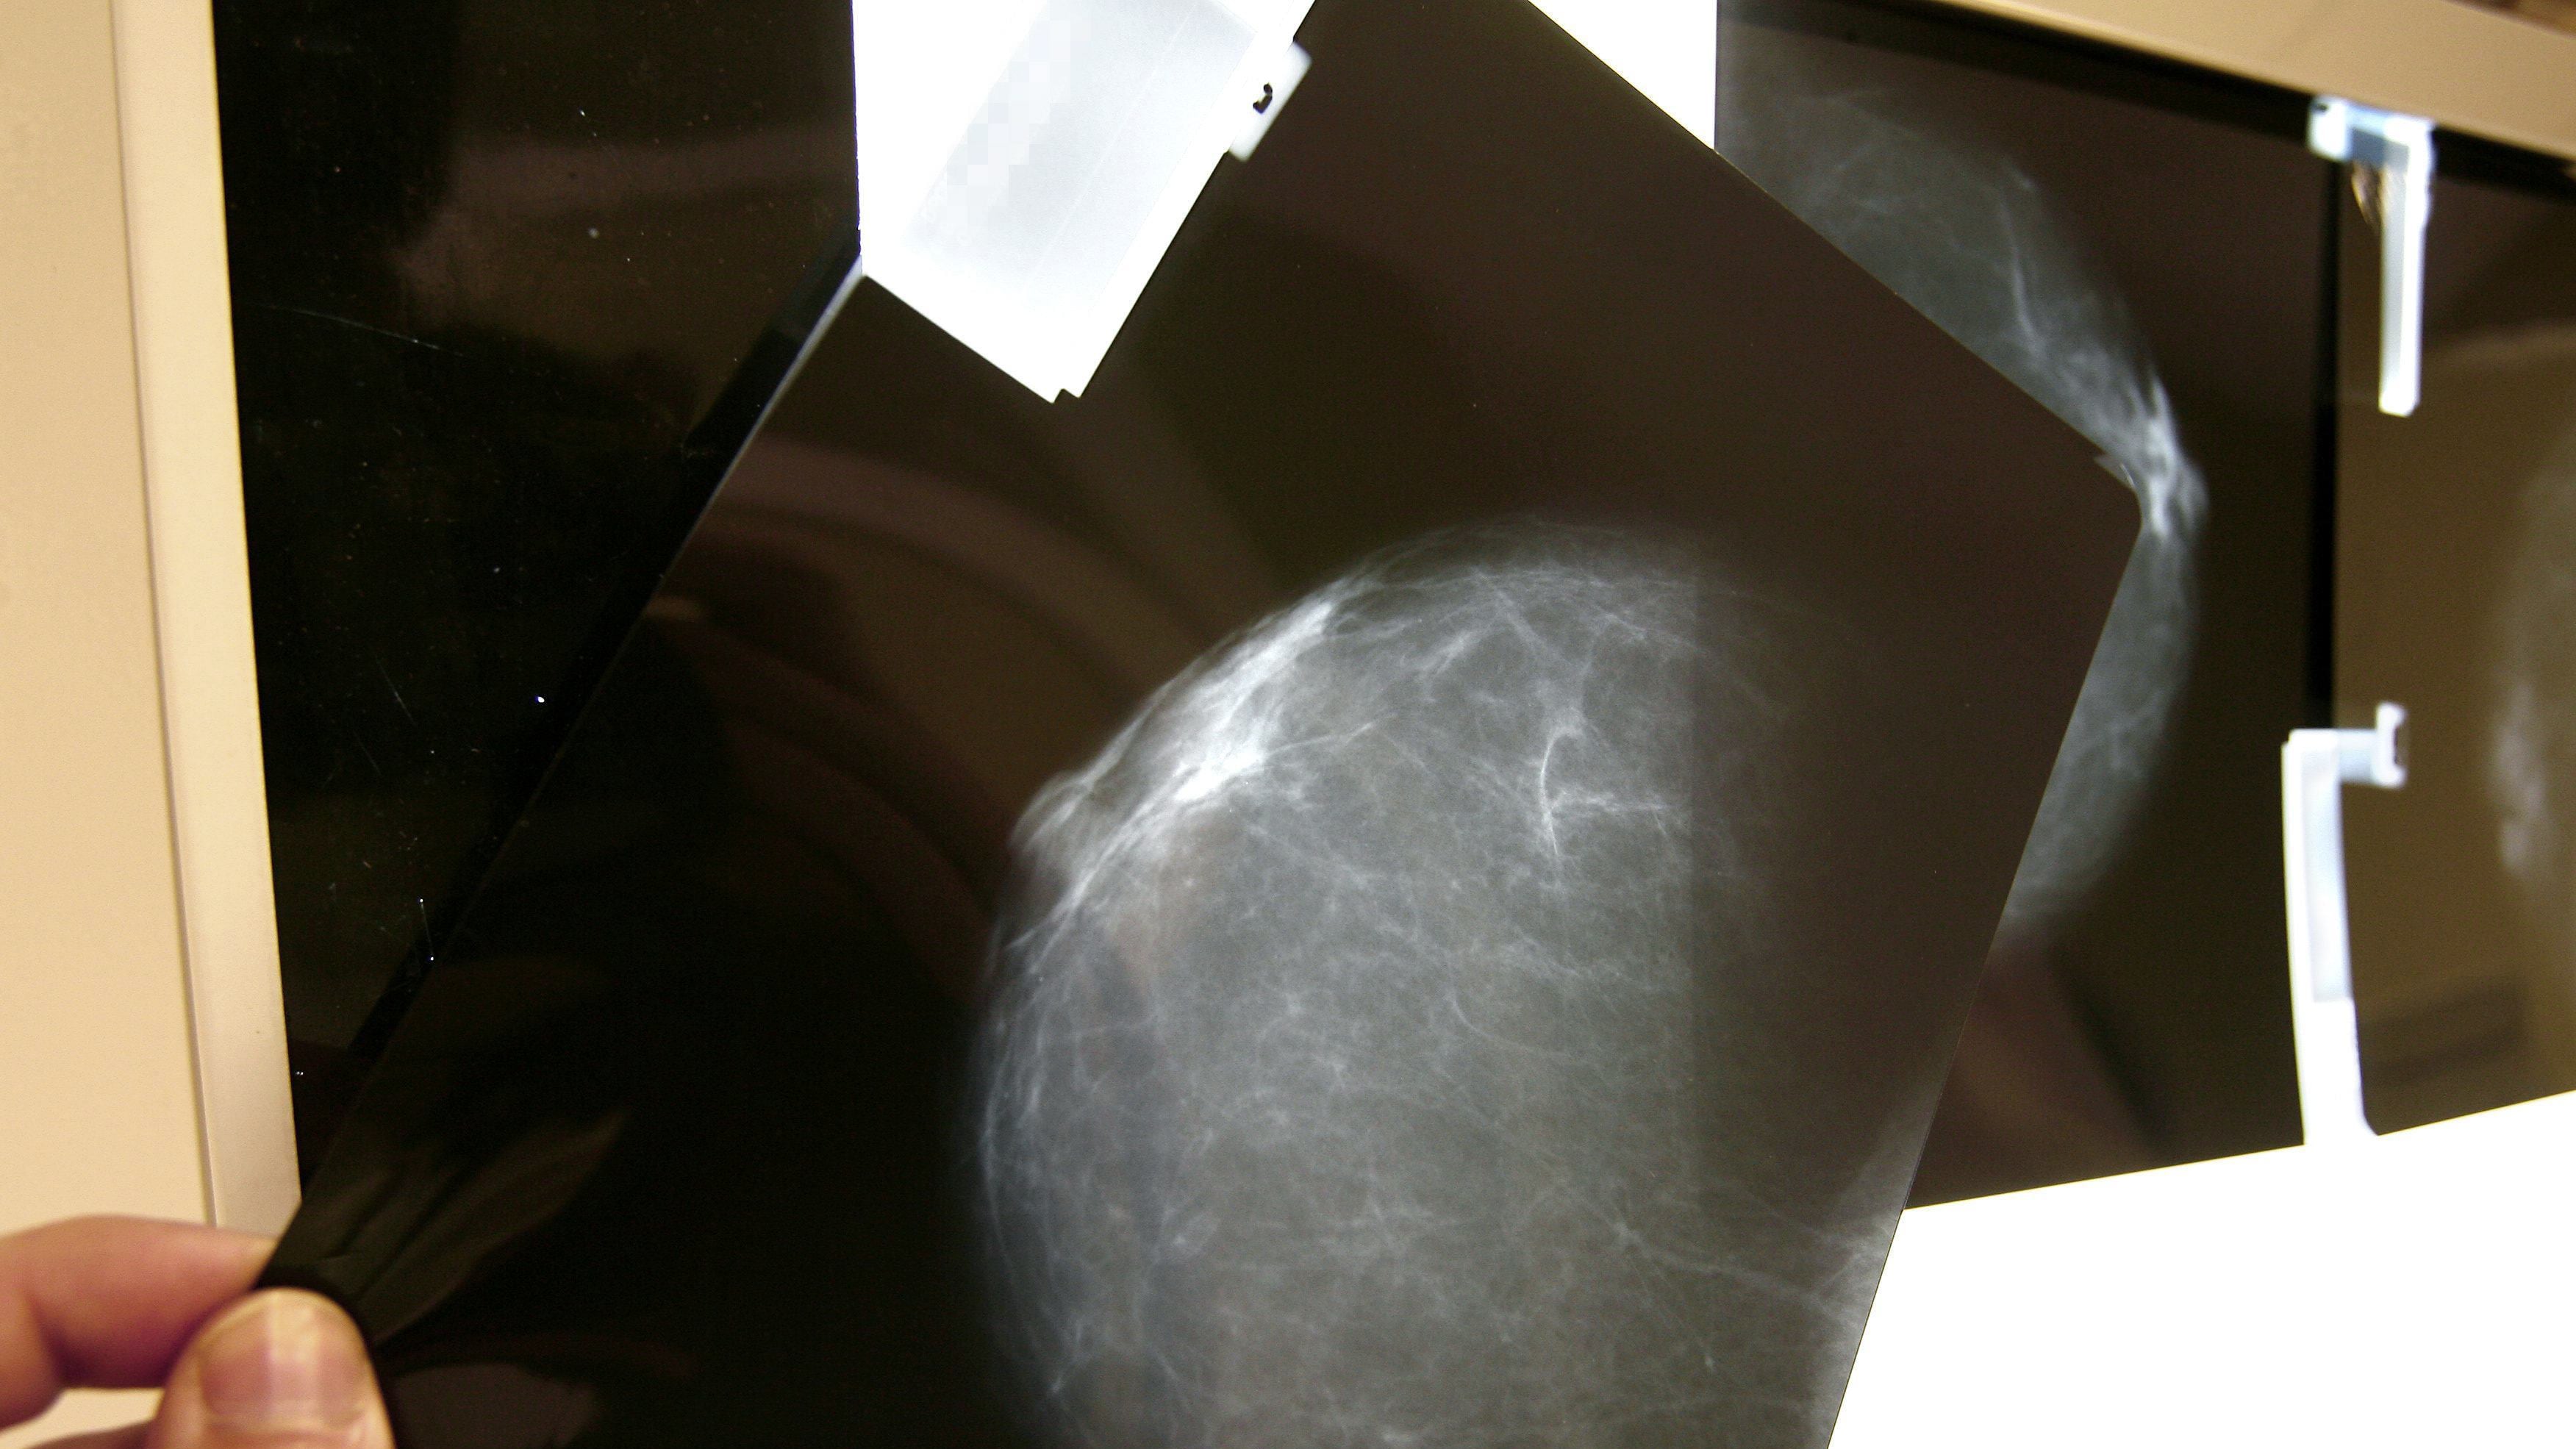

El cáncer de mama en mujeres jóvenes encendió alertas en México, luego de que especialistas señalaran que una proporción significativa de casos se detecta en menores de 40 años, sin protocolos adecuados de diagnóstico temprano.

Miryana Pérez Vela, directora de Fundación de Alba, explicó en entrevista con Publimetro que entre el 11% y el 15% de los diagnósticos anuales de cáncer de mama en el país corresponden a mujeres menores de 40 años.

Este porcentaje, detalló, es superior al registrado en otros países, donde la incidencia en este grupo suele oscilar entre el 7% y el 9%, lo que coloca a México en una situación atípica.

Uno de los principales problemas, señaló Pérez Vela, es que no existen guías clínicas específicas para la detección de cáncer de mama en mujeres jóvenes.

Esto provoca que muchas pacientes no sean sometidas a estudios como mastografías o ultrasonidos en etapas tempranas, lo que deriva en diagnósticos avanzados y menor probabilidad de curación.